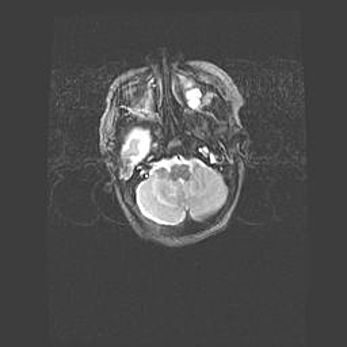

Множественные кисты обоих полушарий головного мозга, наибольшая из них в правой затылочной области. Ассиметричная атрофическая гидроцефалия.

Возраст: 7 месяцев

Вес: 5660 г

Пол: мужской

Окружность головы: 41,5 см

Срок гестации: 28-29 недель

Кисты головного мозга развиваются в результате многоочаговых некрозов вещества мозга и возникают вследствие перенесенной перинатальной инфекции, менингитов, энцефалитов, асфиксии, родовой травмы, расстройств мозгового кровообращения различного генеза. Образованию кист в веществе головного мозга плодов и новорожденных способствуют такие факторы, как высокое содержание в нем воды, недостаточная (или отсутствие) миелинизация и слабая астроглиальная реакция на повреждение.

Кисты могут сочетаться с гидроцефалией и другими поражениями головного мозга.